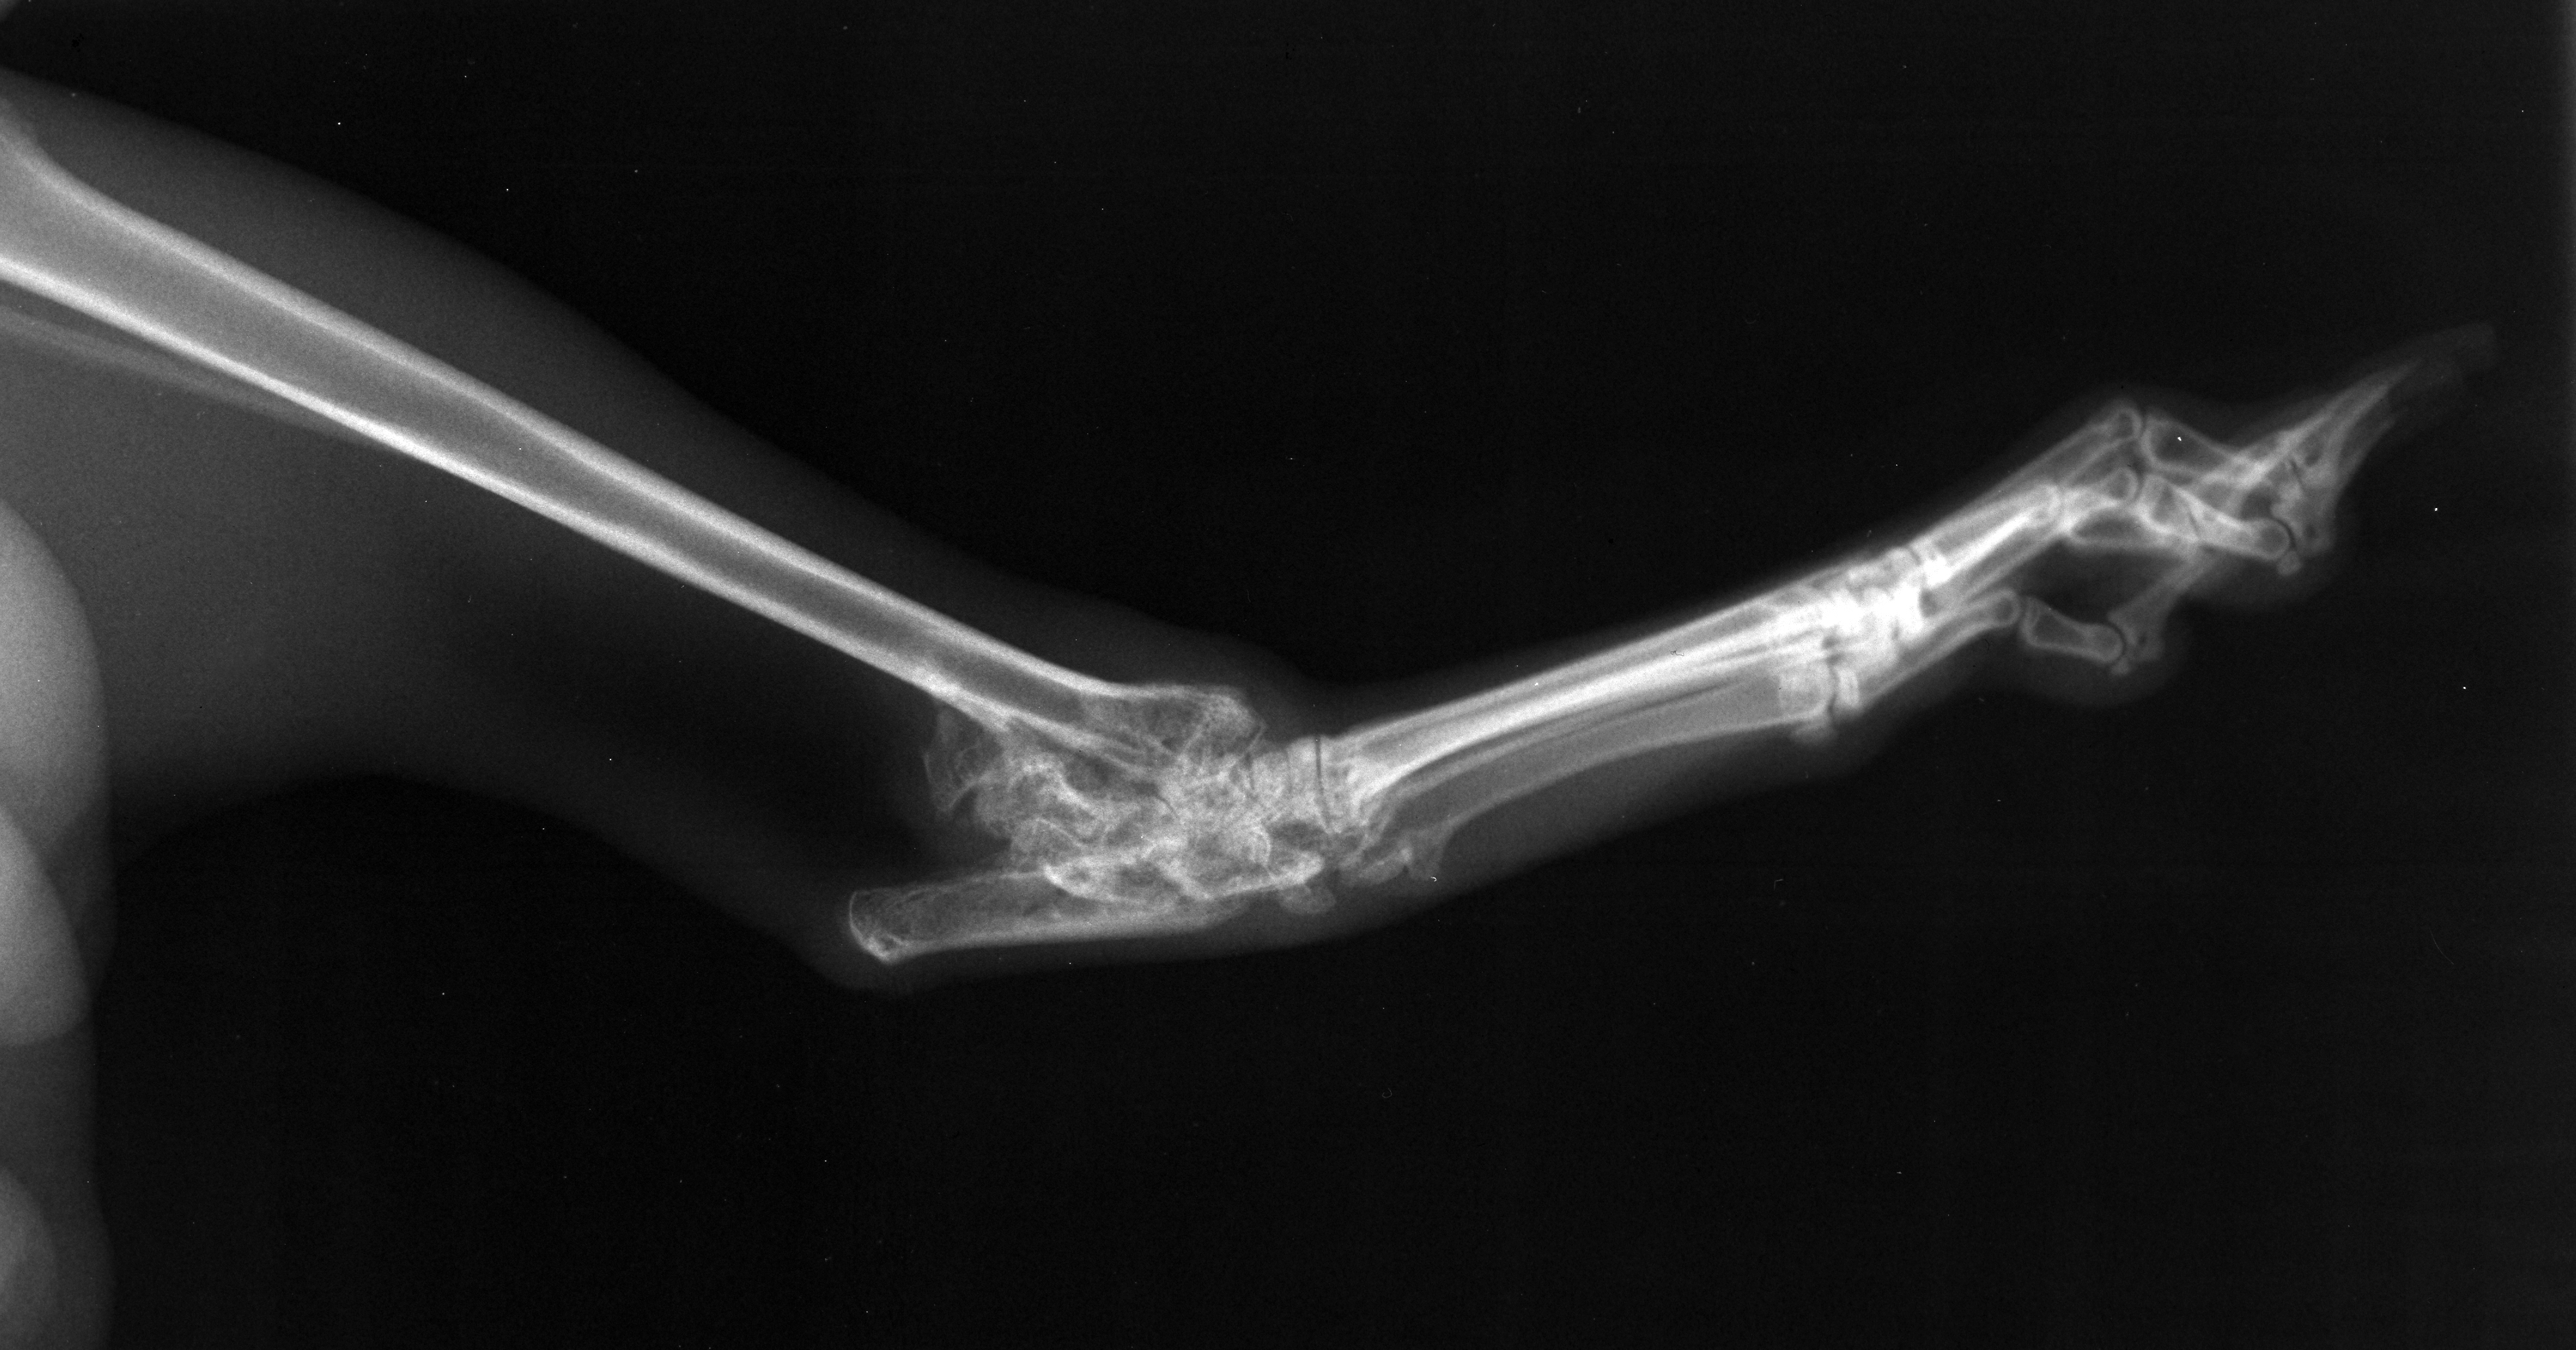

Jack lateral hock

Orthopaedics

Jack

Radiograph